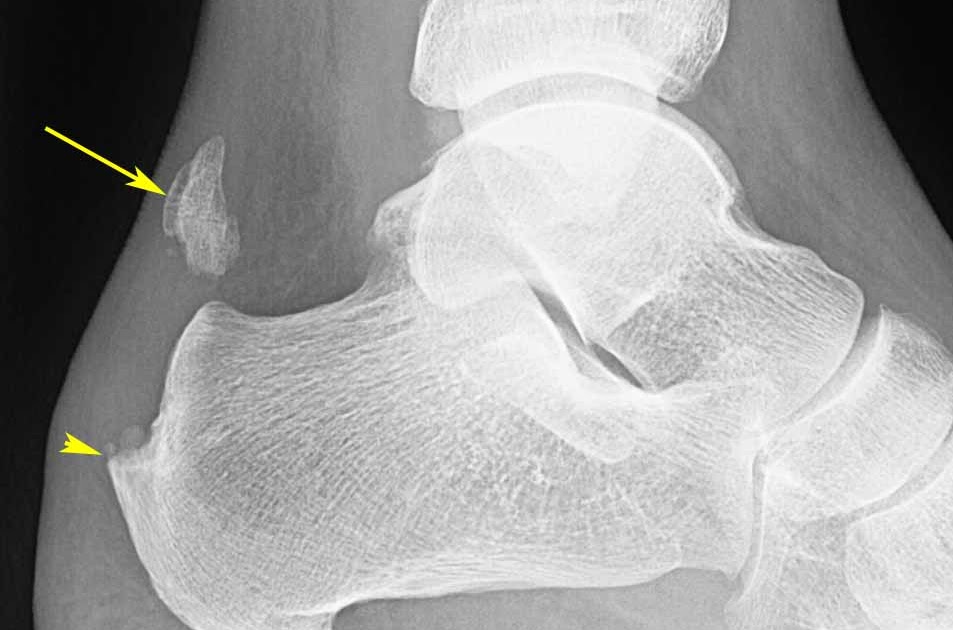

From radiologyinthai.blogspot.com

RiT radiology Achilles Tendon Rupture How Serious Is An Achilles Tendon Rupture an achilles tendon rupture is an injury that is usually painful and likely to affect your ability to walk. an achilles tendon rupture can be serious as you might not be able to walk and it can take time to recover from. risk factors for a rupture of the achilles tendon include poor. what is the. How Serious Is An Achilles Tendon Rupture.